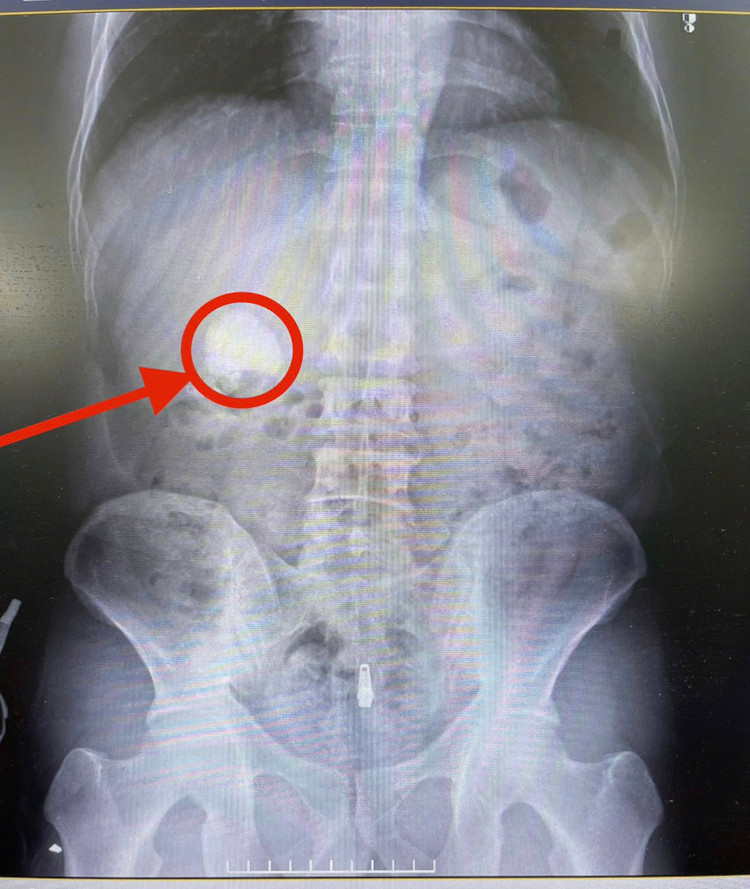

| Hình ảnh sỏi thận trên phim chụp - Ảnh BVCC |

Kết quả chụp cắt lớp vi tính cho thấy nhiều viên sỏi tại thận phải, trong đó viên lớn nhất lên tới 34x39mm, kèm nhiều đám sỏi rải rác tại các đài thận. Trước nguy cơ tổn thương chức năng của thận duy nhất còn lại, các bác sĩ đã hội chẩn và quyết định thực hiện phẫu thuật nội soi tán sỏi qua da đường hầm nhỏ, dưới hướng dẫn của siêu âm.